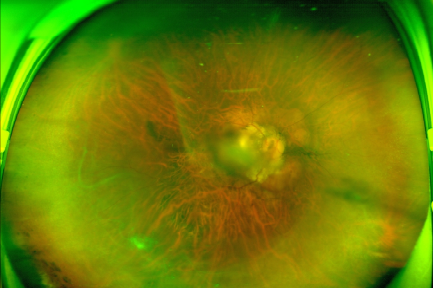

周阿姨的双眼术后眼底照片

经过半年的随访复查,周阿姨的双眼近视度数基本稳定。但深受高度近视折磨的周阿姨下定决心,要通过手术彻底摘掉这个跟随了自己几十年的眼镜。